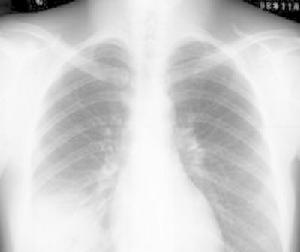

多重肺部感染透視檢查

其他輔助檢查:X線病變範圍更廣泛,壞死性肺炎更常見。